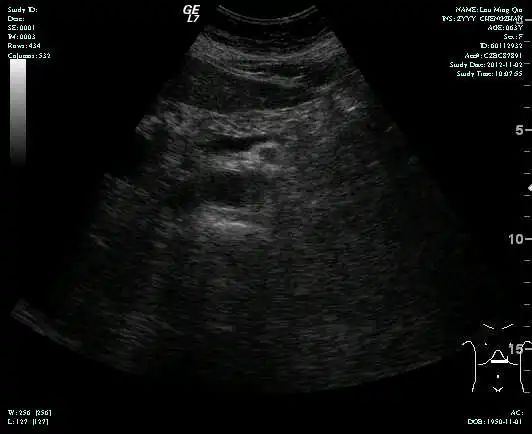

影像学表现:

• CT示:肝转移

• MR示: